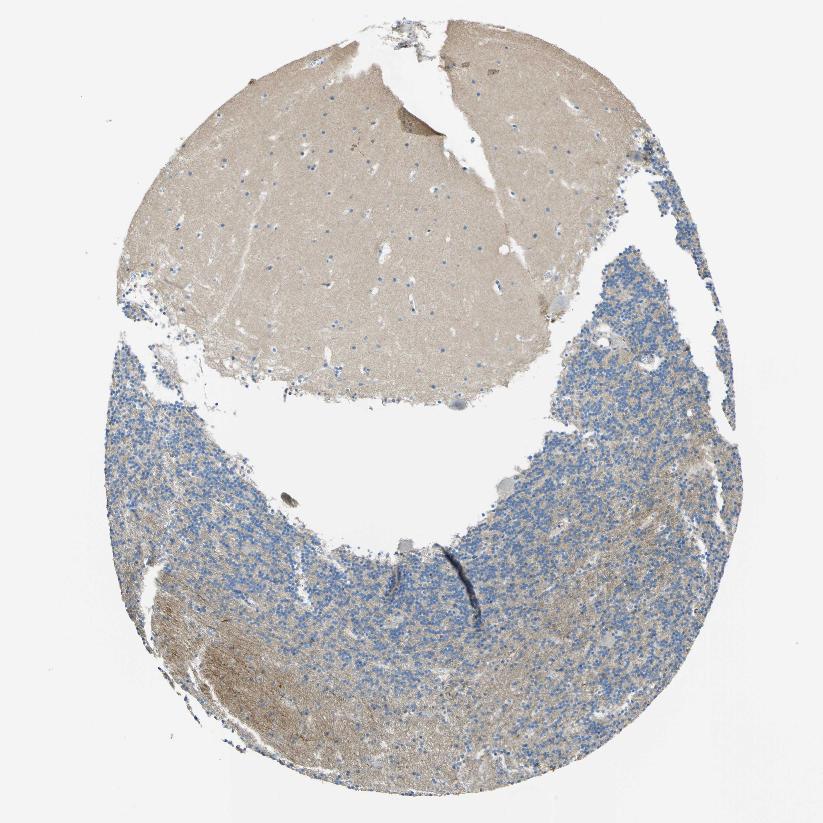

CEREBELLUM - Antibody stainingi

Antibody staining in the annotated cell types in the current human tissue is reported as not detected, low, medium, or high, based on conventional immunohistochemistry profiling in selected tissues. This score is based on the combination of the staining intensity and fraction of stained cells.

Each image is clickable and will lead to virtual microscopy that enables deeper exploration of all samples and also displays staining intensity scores, fraction scores and subcellular localization as well as patient and tissue information for each sample.

Antibody HPA013132

Purkinje cells Not detected

Cells in granular layer Low

Cells in molecular layer Low